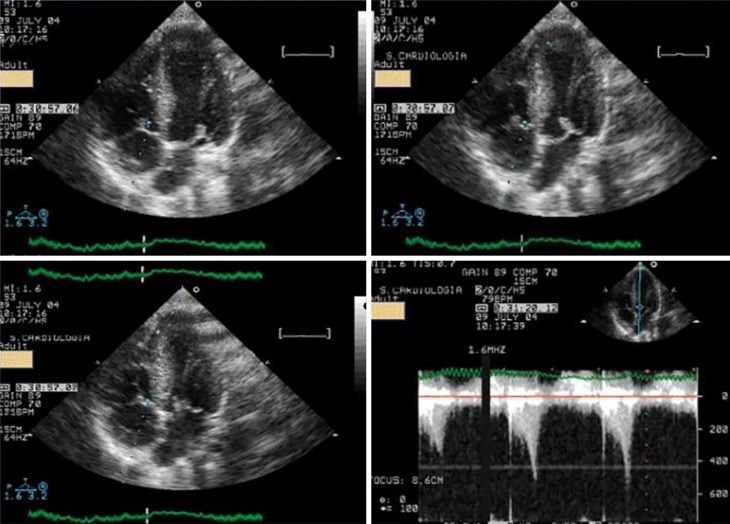

Of the 52 athletes in group 1, 23 (63%) developed systolic anterior motion (SAM) of the mitral valve associated with significant IVG during exercise (Figure 2).

Figure 2.

Systolic anterior movement of the mitral valve and significant intraventricular gradient detected at peak exercise. Citation: Cotrim C, João I, Fazendas P, Almeida AR, Lopes L, Stuart B, Cruz I, Caldeira D, Loureiro MJ, Morgado G, Pereira H. Clinical applications of exercise stress echocardiography in the treadmill with upright evaluation during and after exercise. Cardiovasc Ultrasound 2013; 11: 26 [PMID: 23875614 DOI: 10.1186/1476-7120-11-26] Copyright © The Author (s) 2013. Published by BMC part of Springer Nature.